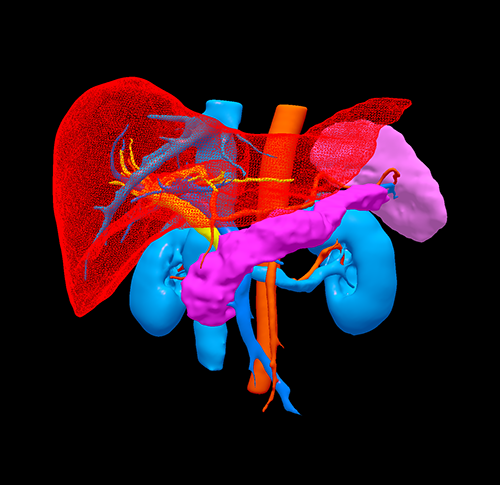

胰头腺癌---胰十二指肠切除